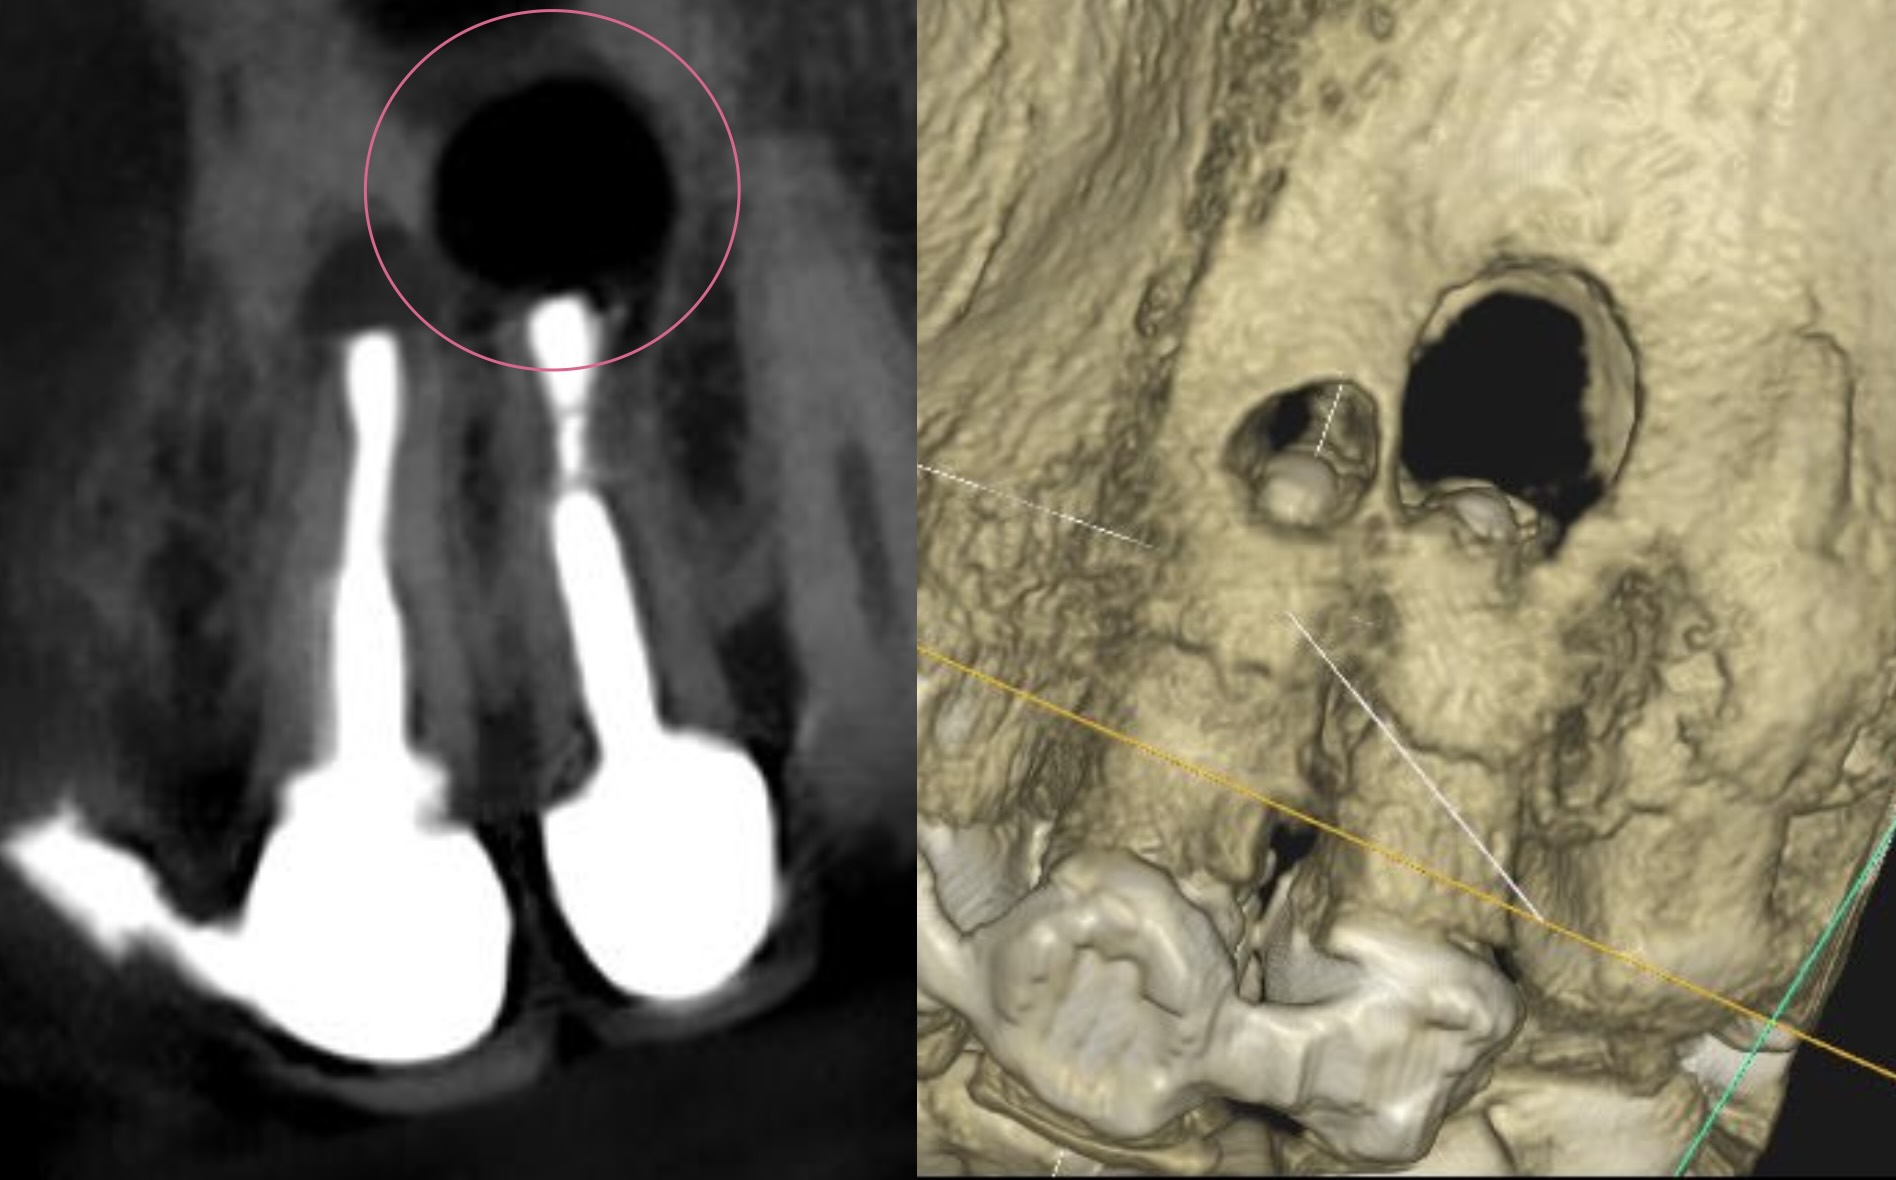

治療前

| 診断名 | pulp diagnosis : Previously treated periapical diagnosis : Chronic apical abscess |

| 治療の方法 |

歯根端切除術 |

根尖部位を予測して、該当する骨を削除。

その後、歯根を約3mm切断。

それぞれの根管を確認

根の先を切るだけでは治りません。

その内部の感染を取り除く処置(逆根管形成)がとても重要になります。

これにより、根管内部の細菌数を減らしています。

外科治療と言っても、やっていること(目的)は、通常の根管治療と同じです。

根管形成後、しっかり封鎖をします。